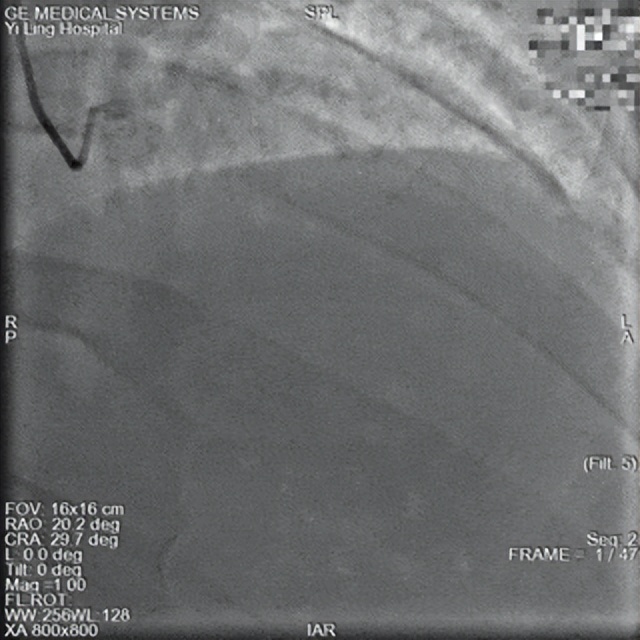

术前

一位55岁男性患者,因反复胸痛入住我院心血管病科,被初步诊断为不稳定性心绞痛,拟于次日行冠脉造影检查。然而住院当日午饭后,患者突发剧烈胸痛伴大汗出,病情急转直下。值班医生立即为其进行心电图复查,提示急性前壁心肌梗死超急性期,随即启动导管室急诊PCI流程。

15时57分,患者进入导管室。急诊冠脉造影显示前降支严重狭窄伴血栓影,需紧急介入治疗。在获得家属知情同意后,心血管病科一病区葛岳鑫副主任迅速为患者前降支置入支架1枚,成功解除狭窄病变。手术于16时17分顺利完成,全程仅用时20分钟。